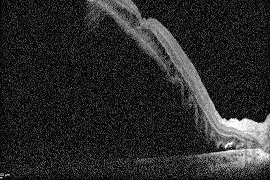

망막박리 수술 전 OCT

망막박리 수술 후 OCT모두다연세안과 배정훈 원장은 대학병원에서 망막 전문 교수로 오랜 기간 환자들을 진료하고 치료해 온 풍부한 임상 경험을 보유하고 있습니다.